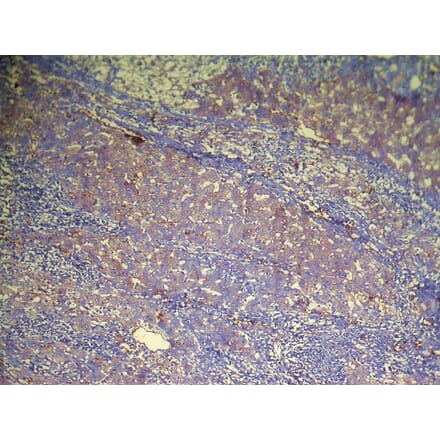

Immunohistochemistry - DHRSX Antibody from Signalway Antibody (42957) - Antibodies.com